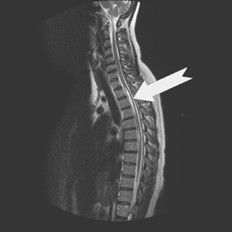

Is een zeldzaam voorkomende aandoening in het ruggenmerg. Hierbij is in het centrale gedeelte van het ruggenmerg een met hersenvloeistof (liquor) gevulde holle ruimte (syrinx) aanwezig die de grijze stof verdringt en zelf geen zenuwcellen bevat. De aandoening komt vooral op het niveau van de hals en borstwervelkolom voor.

Fig. 1 MRI van een syrinx

Er is meestal geen samenhang tussen de grootte van een syrinx en de ernst van de klachten. Ook is er lang niet altijd een eenduidig verband tussen de hoogte waar de syrinx zich bevindt en de soort klachten die iemand ervaart. Daarnaast is ook het beloop meestal niet te voorspellen; soms is er sprake van langzame toename van de syrinx, maar het kan ook zijn dat de syrinx tot aan het levenseinde niet groter wordt en strikt genomen geen syringomyelie is maar een hydromyelie.